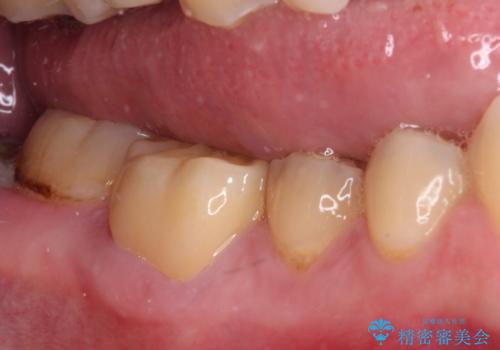

長期海外赴任が近いとのことで、出発に間に合うようにアポイントを調整して治療を進めて行きました。

中途半端に歯冠の見えている親知らずもあったため、そちらも出発前に抜歯を行いました。